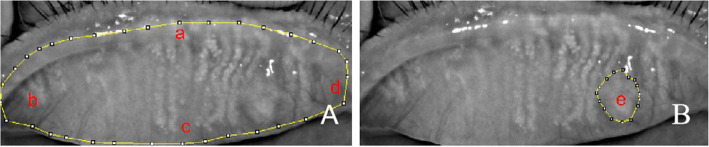

After the eyelids affected by chalazion were everted, a morphological picture was taken by a noncontact infrared meibography system with the Oculus Keratograph (Oculus GmbH, Wetzlar, Germany) as described previously. ImageJ software was used to calculate the area of the chalazion and the whole area of the tarsal plate where the chalazion was located. The proportion of the chalazion area = the chalazion area/the whole area of the tarsal plate (Fig. 1) [11]. The whole area of the tarsal plate was also used to calculate the area at 1 month after complete chalazion resolution; that is, the denominator was unchanged.

Fig. 1.

The method of calculating the proportion of chalazion area in the image of the infrared meibomian gland is shown (a shows the end of the gland at the upper margin of the iliac crest, b shows be the most visible tarsal conjunctiva of the everted lid, c shows the gland at the iliac crest, d shows the nasal border was defined as the tear punctum, e shows the chalazion area). a shows the whole area of the tarsal plate, and b shows the chalazion area

Normal meibomian gland morphology in the chalazion area could not be observed before treatment, but after complete chalazion resolution, meibomian gland loss was observed in the chalazion area with both treatment methods. Moreover, no statistically significant difference between the proportion of meibomian gland loss and the proportion of the initial chalazion area (P > 0.05) was noted in either treatment group (Table 3) (Figs. 2 and 3).

Fig. 2.

The meibography images of chalazion with conservative treatment. a shows the chalazion of meibography image before treatment; b shows the meibomian gland loss at 1 months after chalazion resolution

Fig. 3.

The meibography images of chalazion with surgery. a shows the chalazion of meibography image before surgery; b shows the meibomian gland loss at 1 months after chalazion resolution